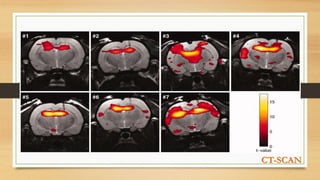

CT-SCAN

• Computerised tomography